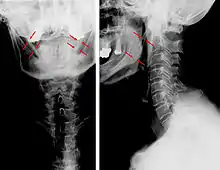

Radiograph, lateral view showing elongated stylohyoid process and stylohyoid ligament ossification

Radiograph, lateral view showing joint-like formation in ossified stylohyoid ligament

Diagnosis is suspected when a patient presents with the symptoms of the classic form of "Eagle syndrome" e.g. unilateral neck pain, sore throat or tinnitus. Sometimes the tip of the styloid process is palpable in the back of the throat. The diagnosis of the vascular type is more difficult and requires an expert opinion. One should have a high level of suspicion when neurological symptoms occur upon head rotation. Symptoms tend to be worsened on bimanual palpation of the styloid through the tonsillar bed. They may be relieved by infiltration of lidocaine into the tonsillar bed. Because of the proximity of several large vascular structures in this area this procedure should not be considered to be risk free.

Imaging is important and is diagnostic. Visualizing the styloid process on a CT scan with 3D reconstruction is the suggested imaging technique.[12] The enlarged styloid may be visible on an orthopantogram or a lateral soft tissue X ray of the neck.